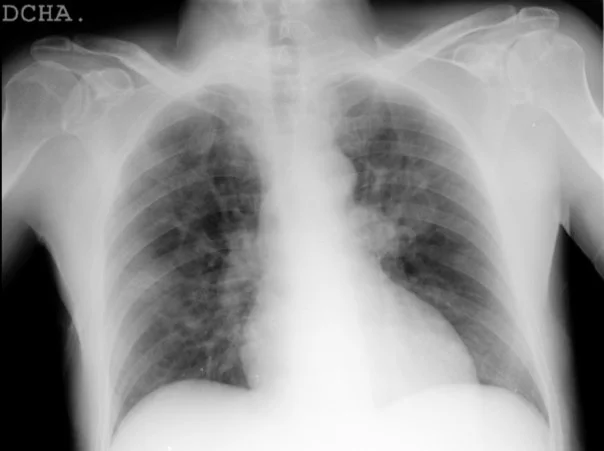

Collaborators Midrc The midrc mrale mastermind grand challenge revealed the potential of ai to assess covid 19 severity from portable cxrs, demonstrating promising performance against the reference standard. Using the medici challenge platform, participants submitted their trained algorithms encapsulated in docker containers. algorithms were evaluated by the challenge organizers on 814 test cases through two performance assessment metrics: quadratic weighted kappa and prediction probability concordance. This article reviews some of the challenges and potential solutions to advance the field forward, with focus on the experience gained by hosting image based competitions. A second midrc grand challenge on covid severity is in the works and will likely kick off in the spring of 2023.

Midrc Data Midrc This article reviews some of the challenges and potential solutions to advance the field forward, with focus on the experience gained by hosting image based competitions. A second midrc grand challenge on covid severity is in the works and will likely kick off in the spring of 2023. Conclusions: the midrc mrale mastermind grand challenge revealed the potential of ai to assess covid 19 severity from portable cxrs, demonstrating promising performance against the reference standard. Rsna’s contribution to midrc includes the rsna international covid 19 open radiology database (ricord), a substantial body of imaging data with annotations and supporting clinical information for use in education and research. Please join us in congratulating the winners listed below and in thanking spie (the international society for optics and photonics) for their generous financial support. a seminar about this challenge is on our channel!. Contribute to midrc midrc grand challenges development by creating an account on github.